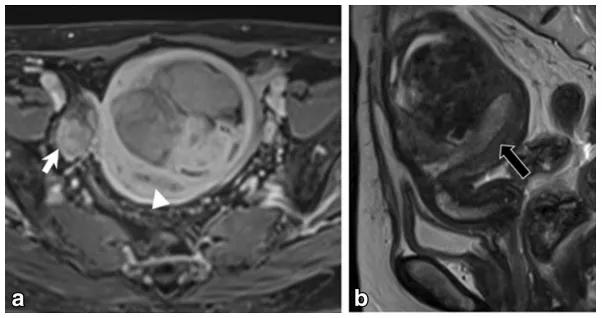

女,68 岁,左卵巢 Brenner 瘤。T2WI 显示左侧卵巢巨大低信号肿物(图 a),CT 扫描显示 8 年后肿物增大、多发钙化、发生囊变(图 b)。

女,50 岁,卵巢甲状腺肿。左卵巢肿物,T2WI 呈不均匀稍高信号(图 a),增强扫描早期明显强化(图 b),CT 扫描显示囊内成份密度稍高(图 c)。